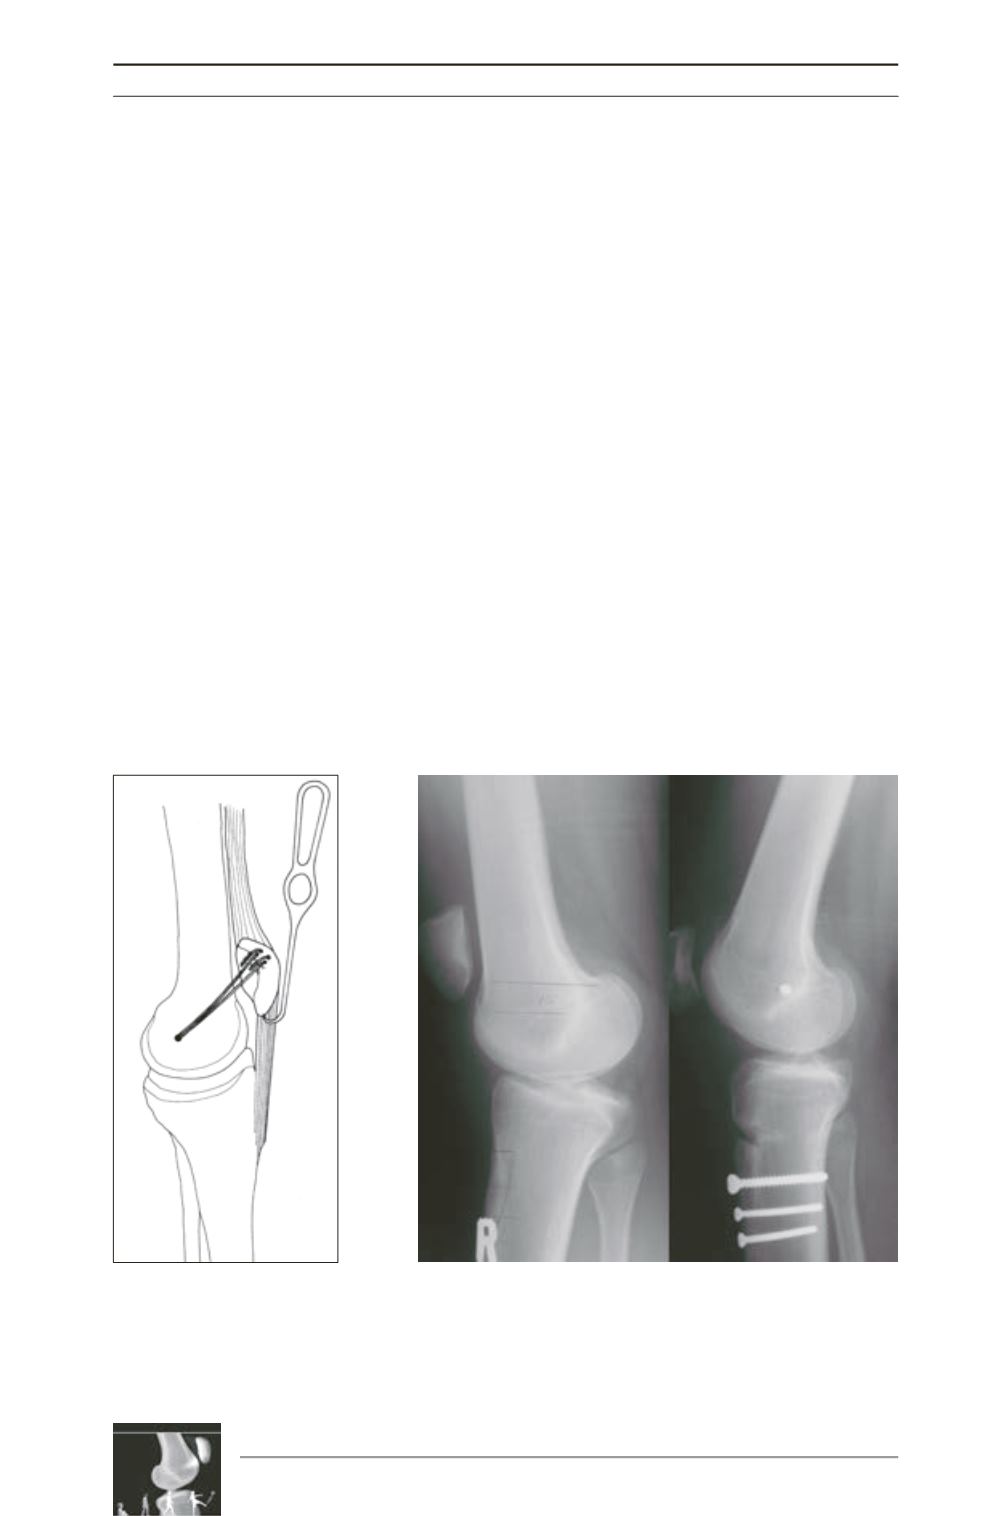

Fig. 3 : Distalization of the tibial tubercle combined with a MPFL

reconstruction.